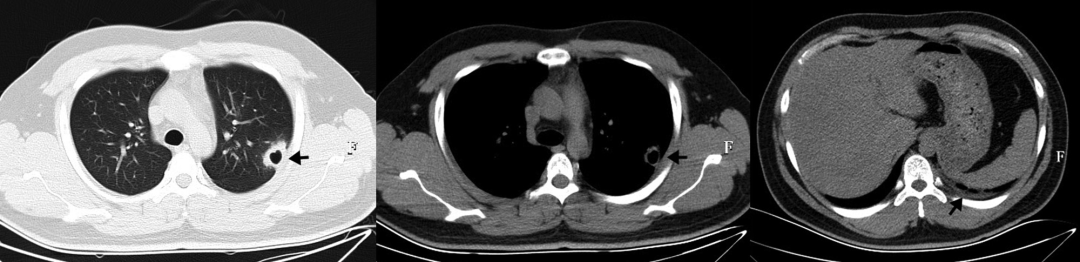

接受静脉注射头孢曲松(2g,每日一次)治疗2周,口服磺胺甲恶唑-甲氧苄啶(0.96g,每日两次)。治疗一周后胸痛缓解。治疗6周后,胸部CT扫描显示肺空洞消失,只留下少量斑片状浸润。胸膜增厚情况有所改善(图2)。

图2:治疗6周后胸部CT显示空洞消失,仅留下少量斑片状浸润,胸膜增厚改善

• 肺部CT显示多灶性双侧毛玻璃影(图3)

图3:入院时肺部CT显示多灶性双侧毛玻璃样阴影